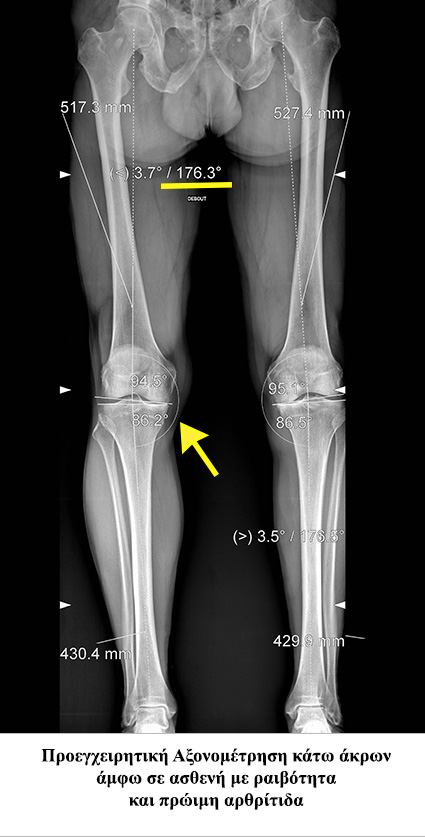

• - Ονομάζεται η απόκλιση του άξονα του γόνατος κατά την οποία η κνήμη και ο μηρός σχηματίζουν γωνία ανοιχτή προς τα έσω. Κατά την παραμόρφωση αυτή τα φορτία του σώματος διέρχονται κυρίως από την έσω πλευρά του γόνατος (έσω μεσάρθριο διάστημα), με αποτέλεσμα αυτό να φθείρεται πιο εύκολα και γρήγορα.

• - Αποτελεί πρώιμο ακτινολογικό δείκτη της αρθρίτιδας του γόνατος.

• - Απλός ακτινολογικός έλεγχος που να περιλαμβάνει και τα δύο κάτω άκρα με σκοπό την ακριβή μέτρηση της παραμόρφωσης.